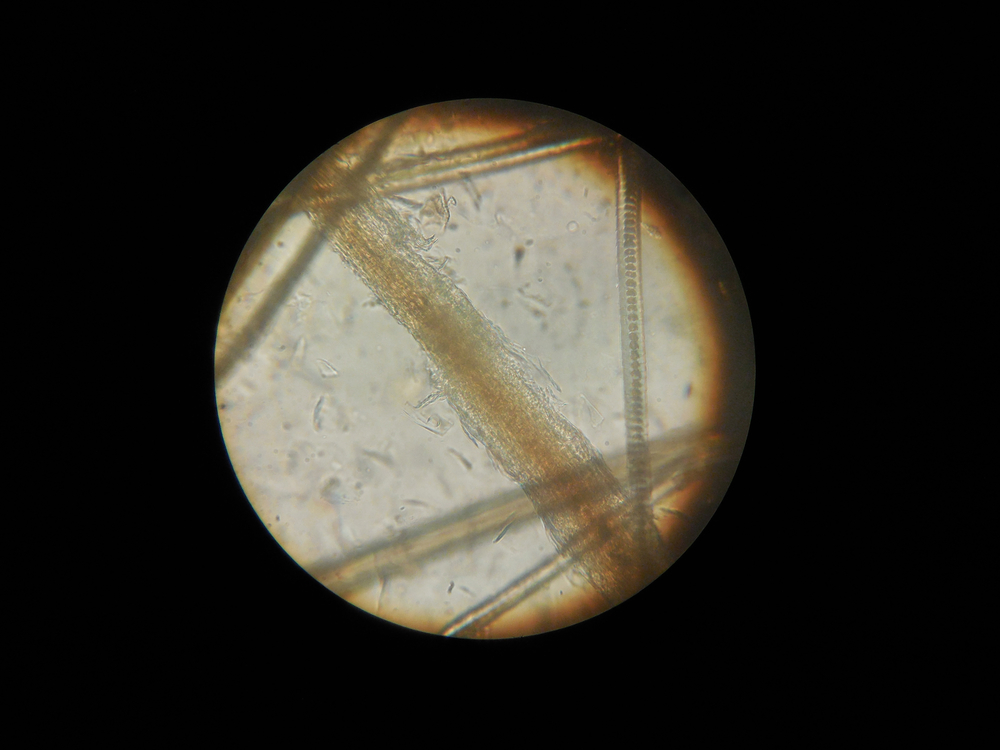

Клинические проявления трихофитии и результаты микроскопического исследования обладают определенными особенностями.

Для того чтобы поставить правильный диагноз, специалист сопоставляет данные клинического осмотра кошки и лабораторных исследований. В лабораторию отправляются соскобы с пораженных участков кожи, которые не подвергались лечению. Паталогический материал вначале микроскопируют, затем высевают на специальные среды. На основании полученных результатов уже ставится окончательный диагноз.

Кроме того, ветеринарный врач в клинике должен посветить пораженные участки кожи, волосяного покрова кошки ультрафиолетовой лампой (лампа Вуда). Обычно при поражении грибами рода микроспорум шерсть дает изумрудно-зеленое свечение, при трихофитии такого свечения не будет.